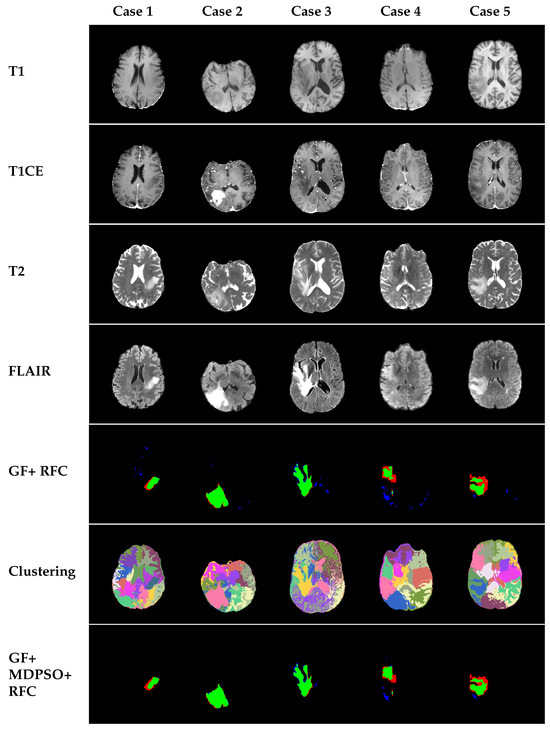

4.3.1. Qualitative Results